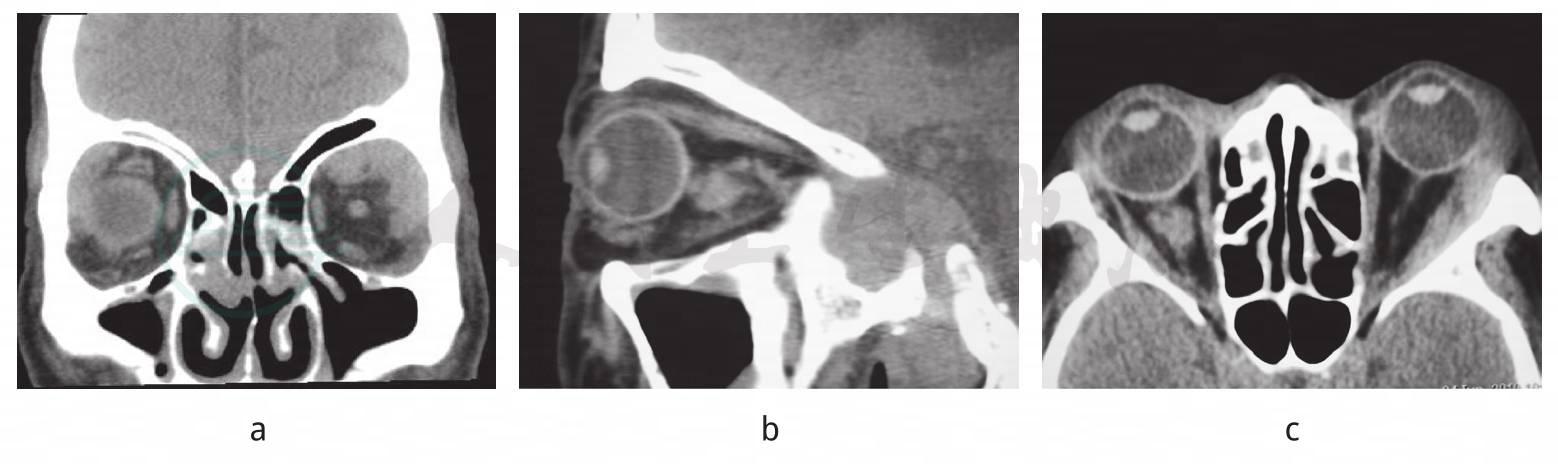

图1 眼眶CT

a~c. 右球后视神经周围团状软组织密度影,边界清晰,欠均质;泪腺轻度肿大;

左泪腺区略扁平三角形软组织密度影,边界清晰,欠均质,沿眶壁向眶尖蔓延,眶骨壁未见明显破坏